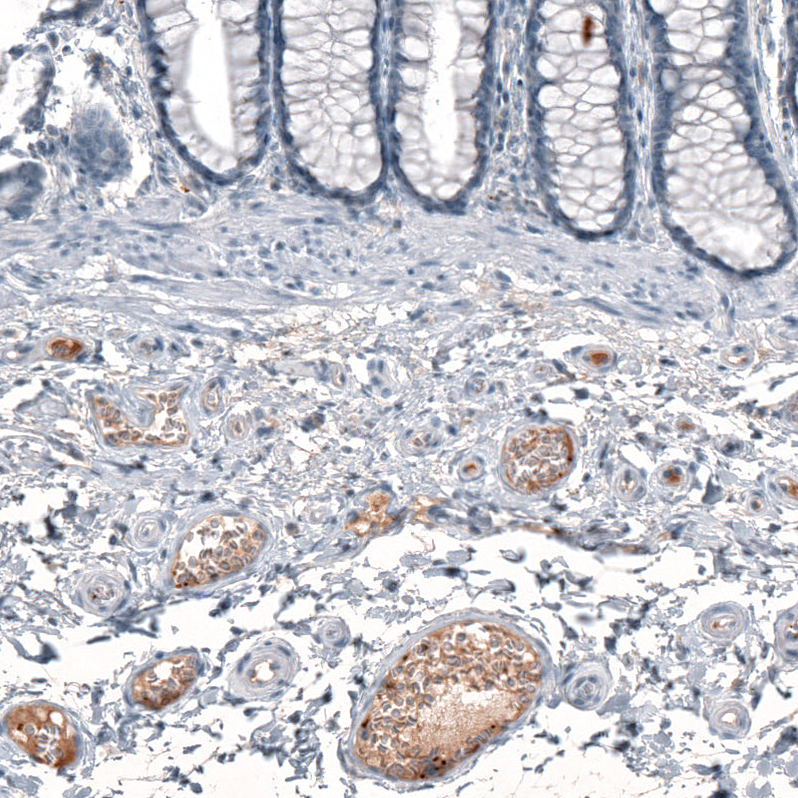

Immunohistochemical staining of human rectum shows moderate positivity in plasma.